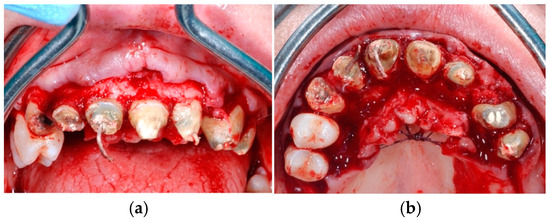

Figure 4. Sites of the test group (right side) (a) filled with deproteinized bovine bone in association with calcium sulphate (b), followed by the placement of a collagen membrane to cover the sites (c).

Figure 5. Sites of the control group (left side) (a) filled with deproteinized bovine bone alone (b), followed by the placement of a collagen membrane to cover the sites (c).

Figure 6. Final sutures (occlusal view).